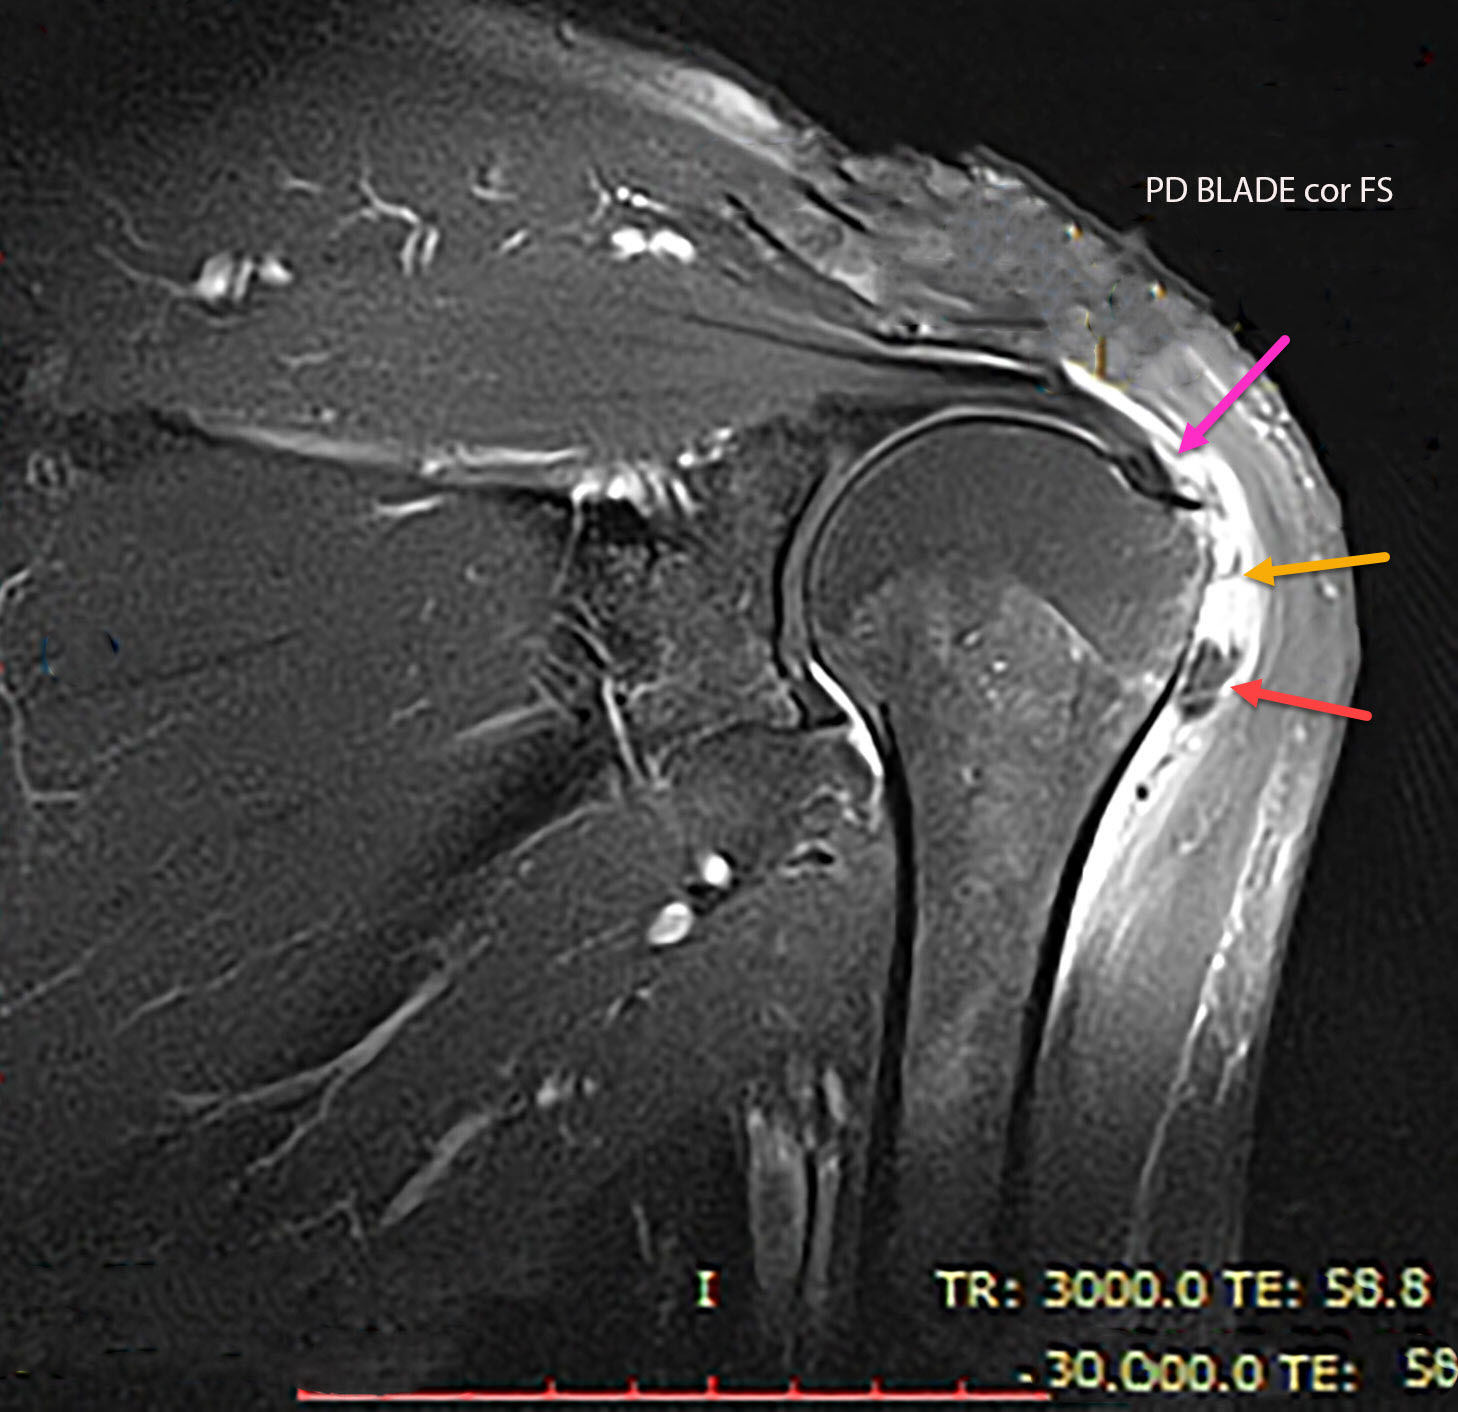

Bursitis MRI wikidoc X Ray Shoulder Bursitis The symptoms of bursitis vary by. Shoulder bursitis (inflammation of a bursa) is one of the leading causes of shoulder pain. It can lead to lost workdays and, in some cases, even disability. Depending on the type of shoulder bursitis, treatment may include activity modification, immobilization with a splint, icing, injections, aspiration of the bursa (removing fluid with a syringe),.. X Ray Shoulder Bursitis.